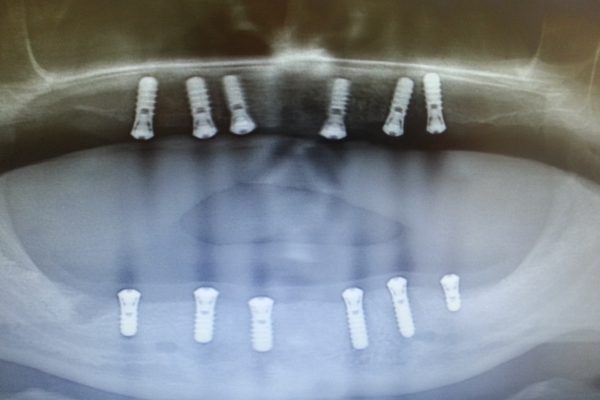

Zahnimplantate

In unserer Partner Klinik werden

bereits

über 10.000

Implantate

eingesetzt.